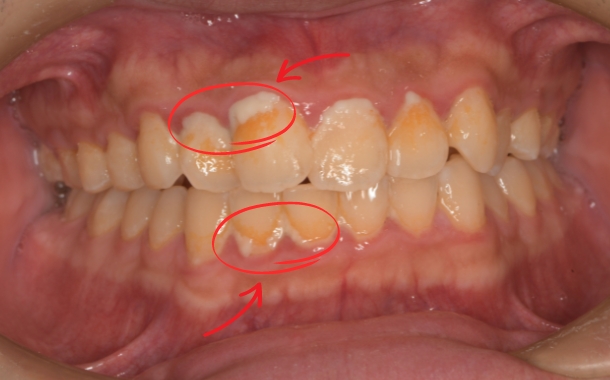

虫歯であれば、黒くなっていたり、痛みが出てきたりなどの症状。

歯周病であれば、歯磨きの時に出血をしていたり、歯茎に炎症があり痛みがあるなどの症状。

お口の中のトラブルは、自覚症状があるまでの間進行し続けています。

痛みや出血が出るまで放置し進行させてしまうと、

最悪の場合神経を取ったり、進行の度合いによっては抜歯という形なるケースも少なくありません。

歯周病であれば、気づいたときには歯がグラグラしているケースもあるため、

自覚する頃には、治療にかなり時間がかかる状態になっているかもしれません。